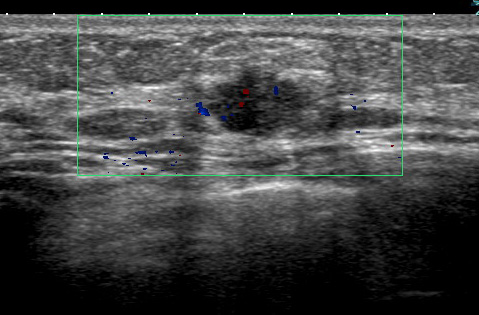

線維腺腫っぽく見えても癌 case.2

同様に左も癌です。

線維腺腫っぽく見えても癌 case.3

これなんかも(左)癌なのだから、やはり「なのは」さんの所見を「線維腺腫だ!間違いない」などというのが如何に無知なことか!